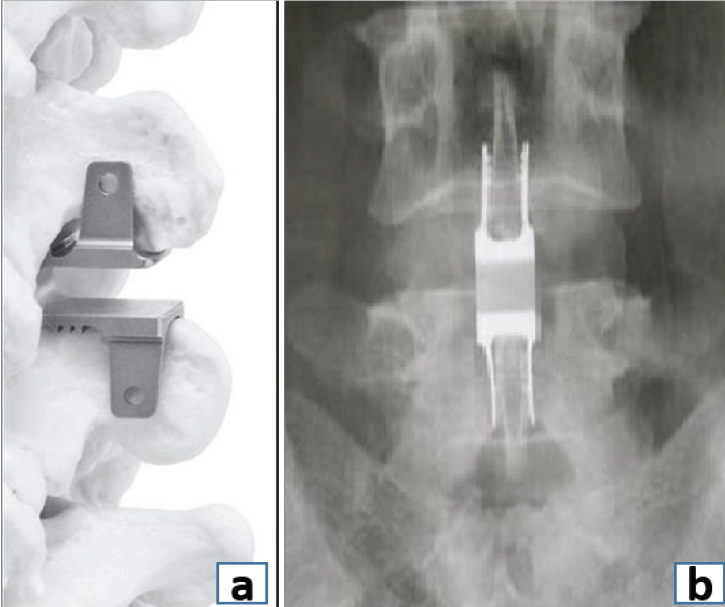

The terms stabilization, fixation, fusion, and reconstruction are frequently used interchangeably amongst spine surgeons. This many times leads to confusion among younger orthopedic, neurosurgeons, and spine surgeons and the multidisciplinary team working along with the spine surgeons. In this editorial, we have tried to analyze and understand this problem by explaining the exact meaning of these terms and where they should be appropriately used (Fig. 1).

Fixation is the mechanical anchorage of the spine with instrumentation to maintain alignment in the face of a potentially destabilizing event, such as a stable fracture with preserved anterior column. Its goal is to immobilize the motion segment and act as a form of primary restraint by creating a scaffold framework that maintains stability until healing occurs. This is achieved using pedicle screws, hooks, sublaminar wires or cables linked by rods and connectors, where bone graft is primarily not used (Fig. 1)

Figure 1: (a) Posterior spinal fixation, (b) Spinal Fusion (interbody), (c) Spinal fixation with fusion, (d) Anteroposterior image demonstrating interbody fusion between the vertebral bodies and posterolateral fusion across the transverse processes.

Fusion is defined as bony continuity between two or more vertebral bodies. Fusion involves preparation of the bony surfaces at the site of intended fusion. Depending on the anatomical location, it can either be interbody fusion, which involves preparation of vertebral endplates and fusion between the two vertebral bodies, or posterolateral fusion, which involves decortication and fusion along the transverse processes.